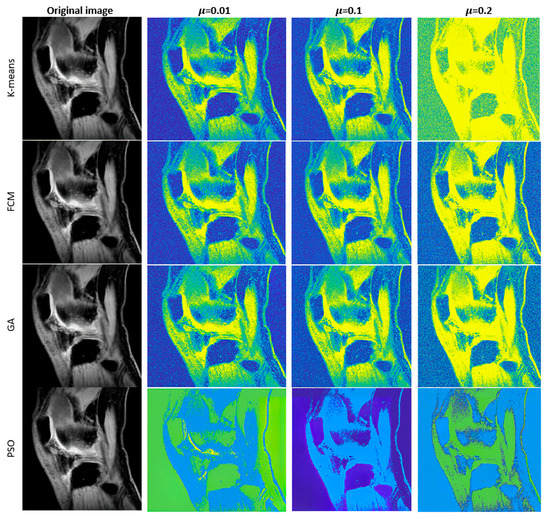

Furthermore, we introduce the graphical comparisons (Figure 4, Figure 5 and Figure 6) of the noise influence on segmentation performance. As we outlined earlier, we designed the analysis, which evaluates the dynamical effect of the noise influence on the segmentation performance. For this purpose, we used three noise generators: Gaussian, Speckle, and Salt and Pepper noise with variable intensity.

Figure 4. Examples of multiregional segmentation maps for optimized clustering schemes with a genetic algorithm (GA) and a PSO with K-means and FCM-based clustering for 4 regions where segmentation is influenced by Gaussian noise with 3 various intensity levels: σ 2 = 0.01 ,   μ = { 0.01 ,   0.1 ,   0.2 } .

Figure 5. Examples of multiregional segmentation maps for optimized clustering schemes with a genetic algorithm (GA) and a PSO with K-means and FCM-based clustering for 4 regions where segmentation is influenced by Speckle noise with 3 various intensity levels: σ 2 = { 0.01 ,   0.1 ,   0.2 } .

Figure 6. Examples of multiregional segmentation maps for optimized clustering schemes with a genetic algorithm (GA) and a PSO with K-means and FCM-based clustering for 4 regions where segmentation is influenced by Salt and Pepper noise with 3 various intensity levels: d = { 0.01 ,   0.1 ,   0.2 } .

Judging by a visual comparison of individual noise generators, the higher the applied noise intensity, the higher the influence on segmentation performance. Nevertheless, just based on the visual comparison, the differences among individual noise types are notable. Significant differences are notable between Speckle and Gaussian noise on the one side and Salt and Pepper noise on the other side, where noise has a higher impact on the segmentation performance. This is caused by the impulse character of the noise, which worsens segmentation performance.